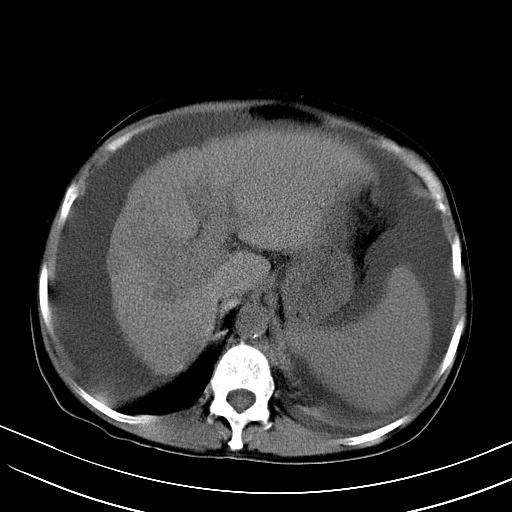

标题: CT23697:肝癌并肝动静脉漏? [打印本页]

标题: CT23697:肝癌并肝动静脉漏?

1)肝右叶肝癌并肝动静脉漏。2)肝硬化,腹水。3)胆囊炎。

肝右叶肝癌并动静脉漏,肝硬化,腹水。

1)肝右叶肝癌并肝动静脉漏 门v右支瘤栓伴海绵样变。2)肝硬化,脾大 腹水。3)胆囊炎。门v高压.

1)肝右叶肝癌并肝动静脉漏。2)肝硬化,腹水。3)胆囊炎。 4,脾大,脾囊肿

右叶肝癌并肝动静脉漏(动脉期肝动脉及门静脉内均可见造影剂),肝硬化,腹水。(胆囊壁水肿)

1)肝右叶肝癌,考虑并发肝动静脉漏。扫描时间好像慢了。2)肝硬化,门脉高压、脾大、腹水。